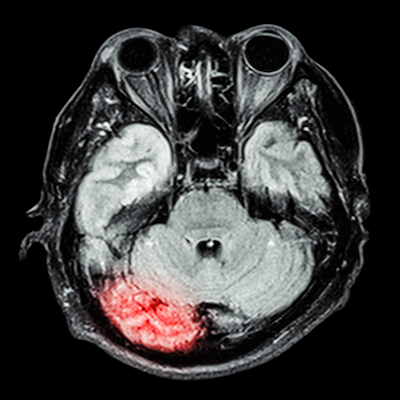

The software upgrade offers improved image quality for Swoop's diffusion-weighted imaging (DWI) sequence by expanding its denoising capability, the company said.